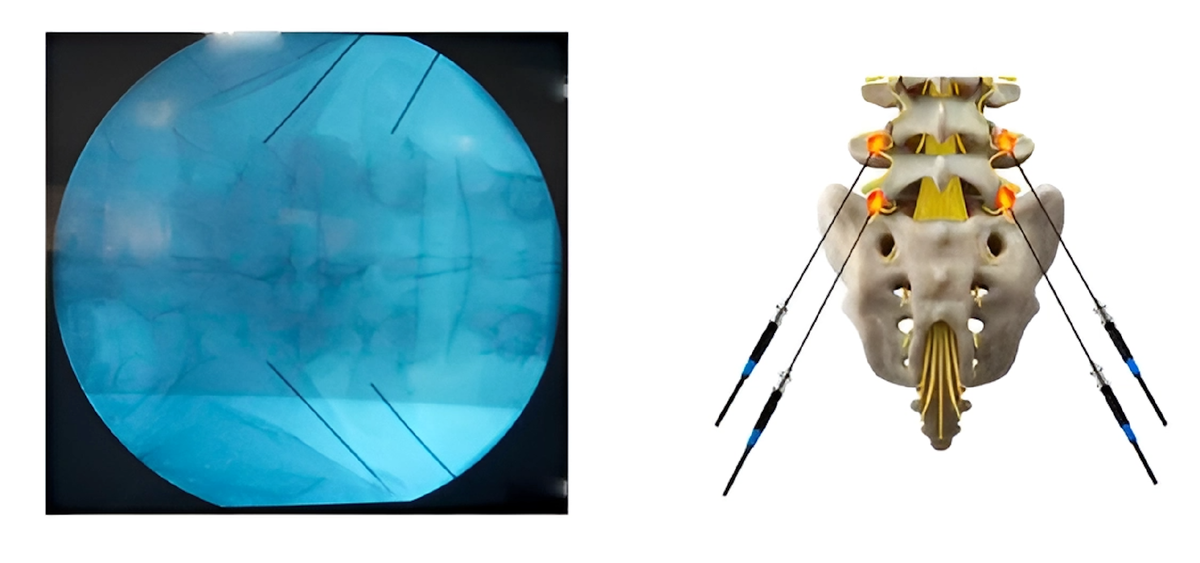

Затем происходит введение иглы в пораженный участок спины или шеи. В процессе данной процедуры, для улучшения визуализации используется рентген – контроль, чтобы помочь специалистам найти пораженное воспалением место.

Ваш врач может пропустить через иглу небольшой электрический ток, чтобы убедиться, что она находится в нужном месте. Также он может спросить, что вы чувствуете. Вы можете почувствовать покалывание или подергивание мышц спины, если игла находится рядом с нервом, вызывающим проблему.